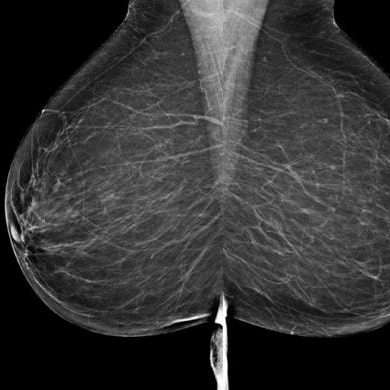

Contrôle de la qualité en mammographie

Le MSSS avait besoin d’une solution efficace pour gérer le contrôle de la qualité des mammographies numériques dans le but d’améliorer la précision diagnostique et la sécurité des patients.

Le CIMMI a conçu et développé CQ-Mammo, un logiciel permettant aux technologues radiologues de planifier et d’exécuter le contrôle qualité sur les équipements de mammographie numérique, ainsi que de produire des rapports conformes aux standards ministériels. Cette solution est devenue une exigence dans la province, étant déployée dans plus de 200 centres médicaux au Québec pour standardiser et améliorer le contrôle de qualité des mammographies.